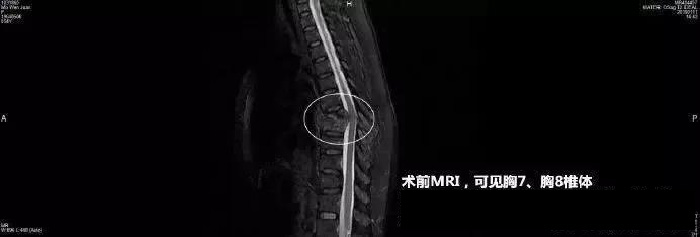

接诊后,医生给陈女士做了胸片检查,检查发现陈女士脊柱有一大块阴影,有可能是骨结核。通过 CT 检查发现,陈女士的胸 7、胸 8 椎体有一个大空洞, 就像被蛀虫咬了一样,整个椎体都塌了下来,导致脊椎的棘突凸起。这就是她背上有一个明显凸起的原因所在。

经过进一步检查发现,导致陈女士脊柱被掏空的原因竟然是 " 结核 " ——一种经常发生在肺部的传染病。陈女士中招的却是脊柱,也就是所谓的 " 骨结核 "。肺结核一般有咳嗽、咳痰、咯血、胸痛等症状,而骨结核症状则比较隐匿。由于早期未发现时结核病,结核细菌在陈女士体内不断破坏,骨关节和脊椎骨质被侵蚀,最终就像骨头被掏空一样。

" 随着疾病的进展,关节活动逐渐受限,最终出现了成角后凸畸形。" 刘少喻教授介绍说," 如果疾病进一步发展,一旦脊髓受到压迫、损伤或牵拉,就有可能导致瘫痪!"